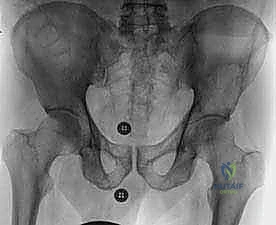

- التصوير بالأشعة السينية (X-rays): الفحص المبدئي لرصد أي تآكل أو تدمير في البنية العظمية للحوض ومفصل الورك.

- التصوير المقطعي المحوسب (CT Scan): يقدم صوراً ثلاثية الأبعاد تُظهر بدقة متناهية مدى تدمير القشرة العظمية، وهو الفحص الأهم للتخطيط الجراحي وتحديد خطر حدوث الكسور المرضية.

التقييم البيوميكانيكي هو تخصص دقيق. يستخدم الدكتور هطيف معايير علمية (مثل معايير هارينغتون Harrington Criteria) لتحديد ما إذا كان عظم الحُق أو الحوض على وشك الانهيار.

* الكسر المرضي الفعلي: إذا انكسر الحوض بالفعل، فإن الجراحة ضرورية لتثبيت العظم المكسور والسماح للمريض بالحركة.

* الكسر الوشيك: إذا أظهرت الأشعة المقطعية أن الورم قد دمر أكثر من 50% من قشرة العظم المحيطة بمفصل الورك، أو تسبب في ألم شديد عند تحميل الوزن، فإن التدخل الاستباقي لمنع الكسر أسهل وأكثر نجاحاً من محاولة إصلاح كسر قد حدث بالفعل.